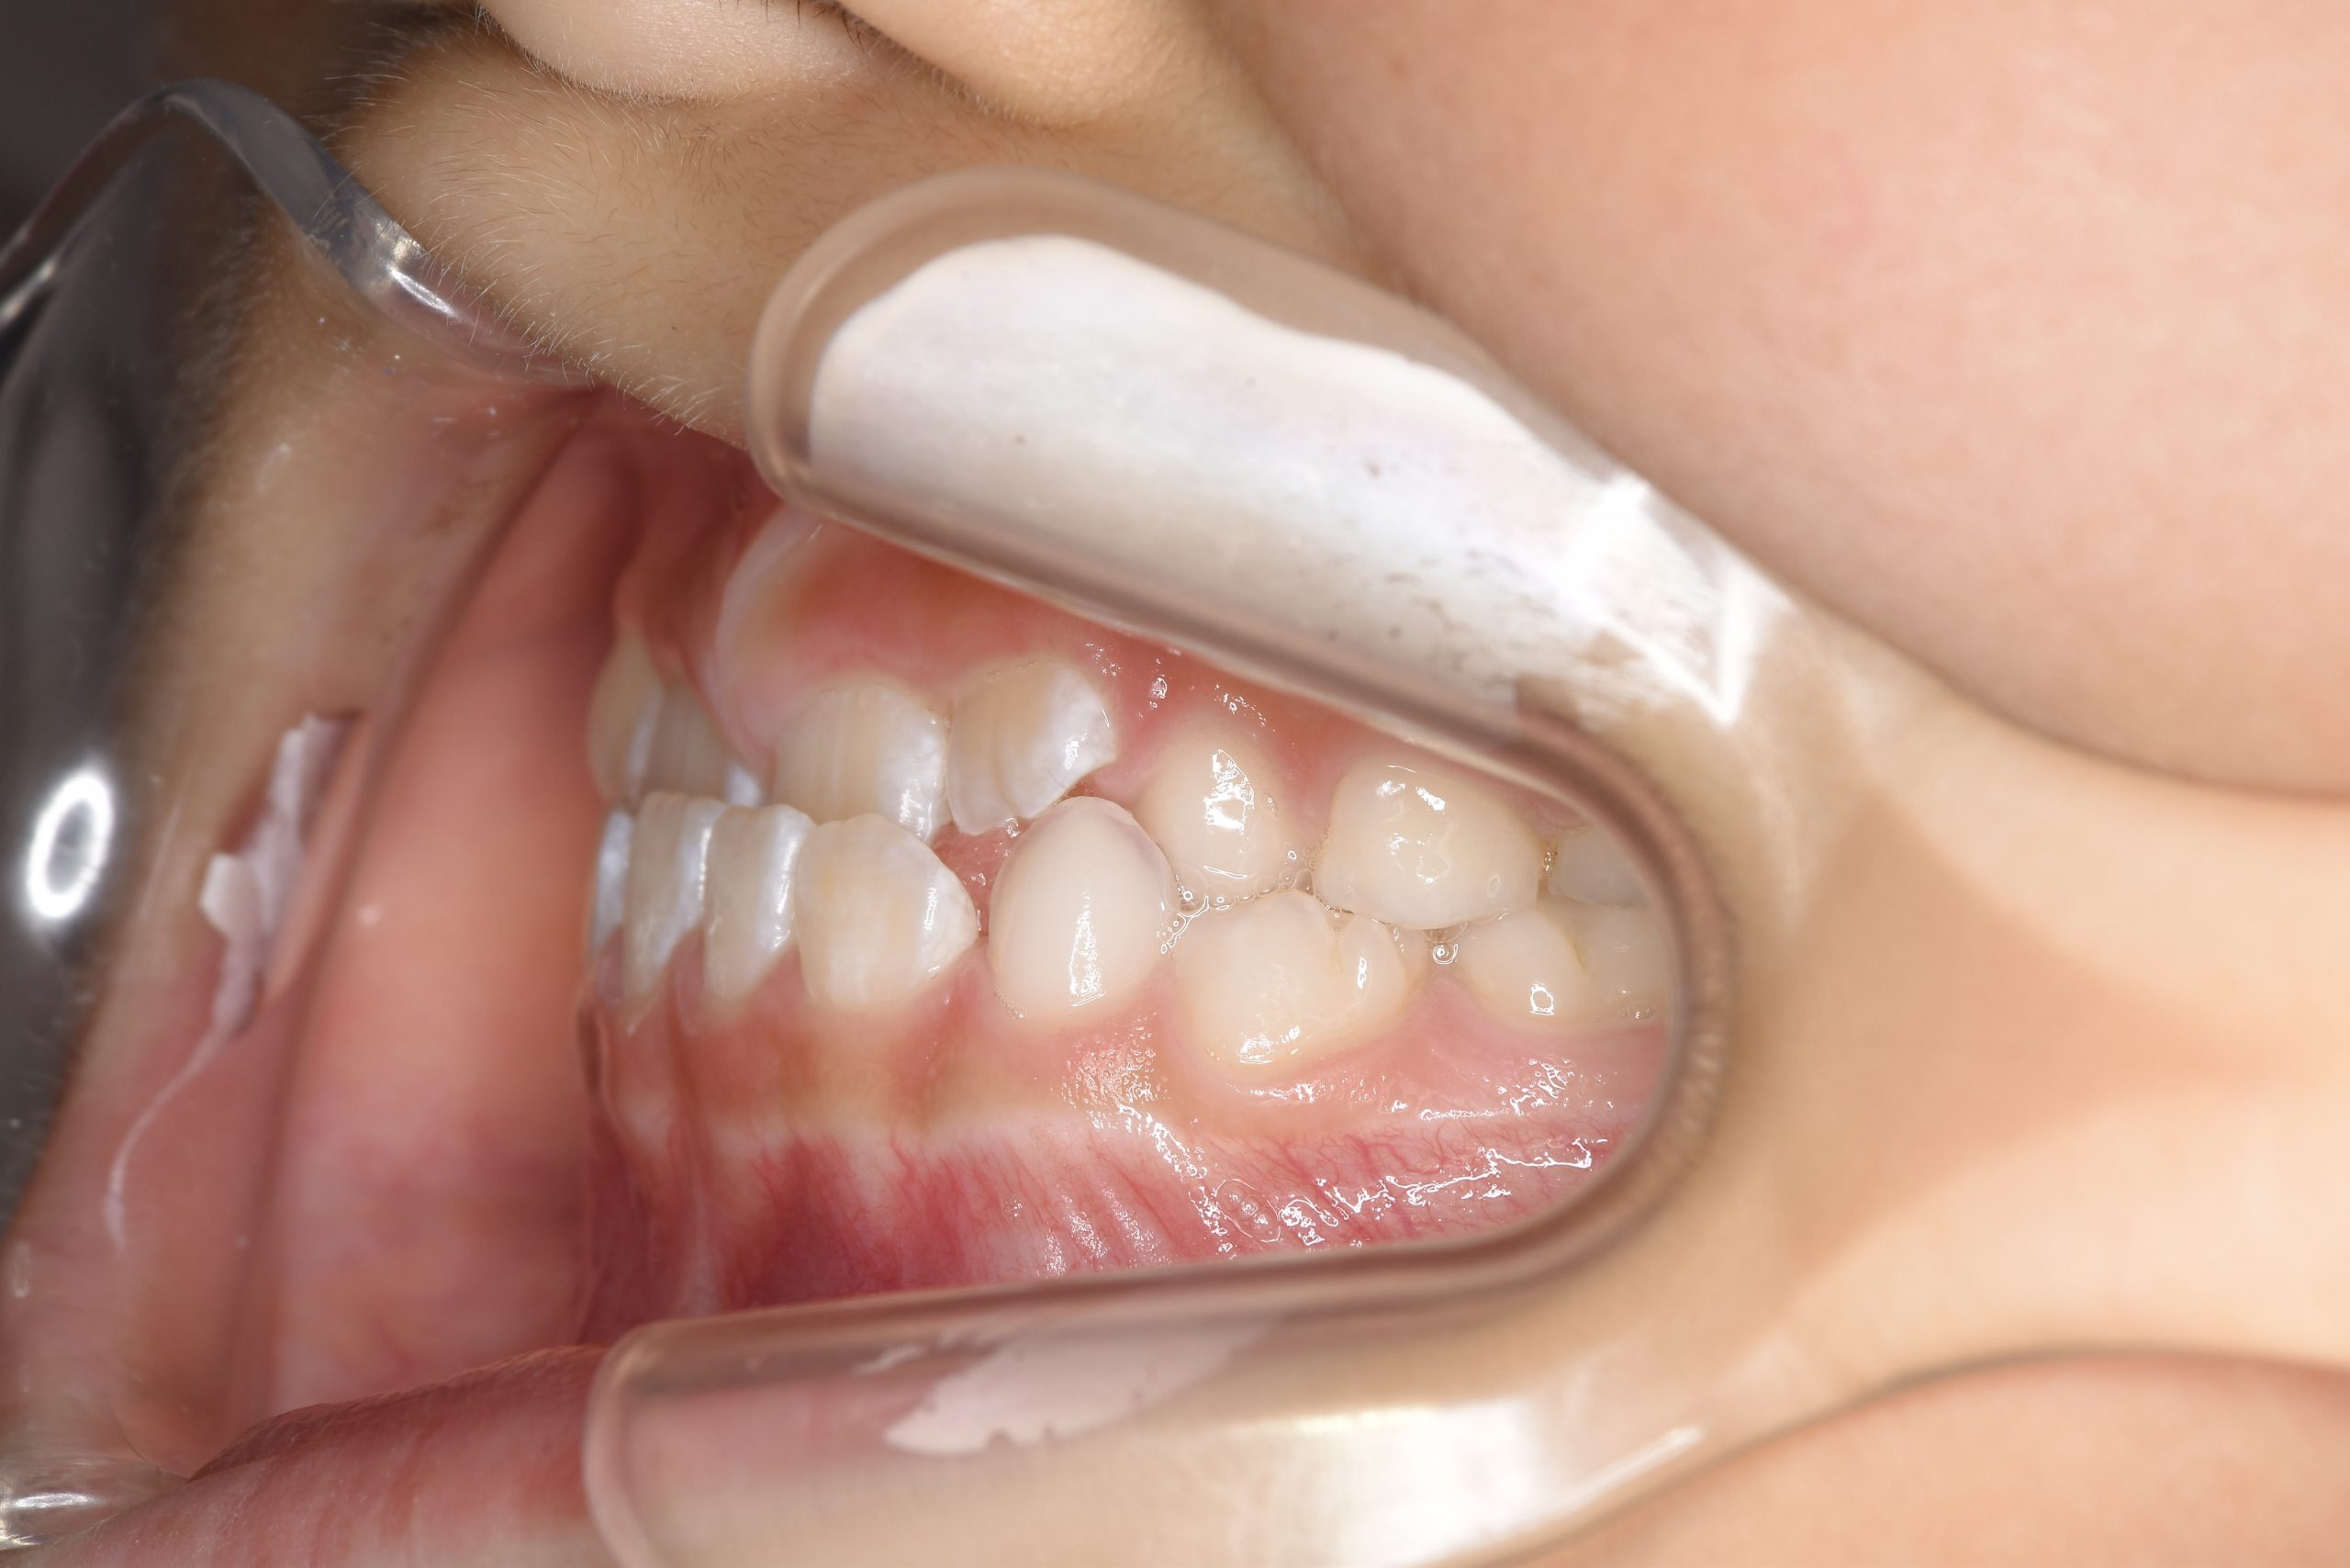

ビフォー

子どもの矯正治療|症例_858

主訴 下顎が出ている

施術内容 上顎急速拡大装置と下顎リンガルアーチを用いて上下顎骨を拡大した。

上顎前方牽引装置を用いて上顎骨を前方に成長促進させた。

その後マウスピース型矯正装置で歯牙を配列し良好な咬合を獲得した。